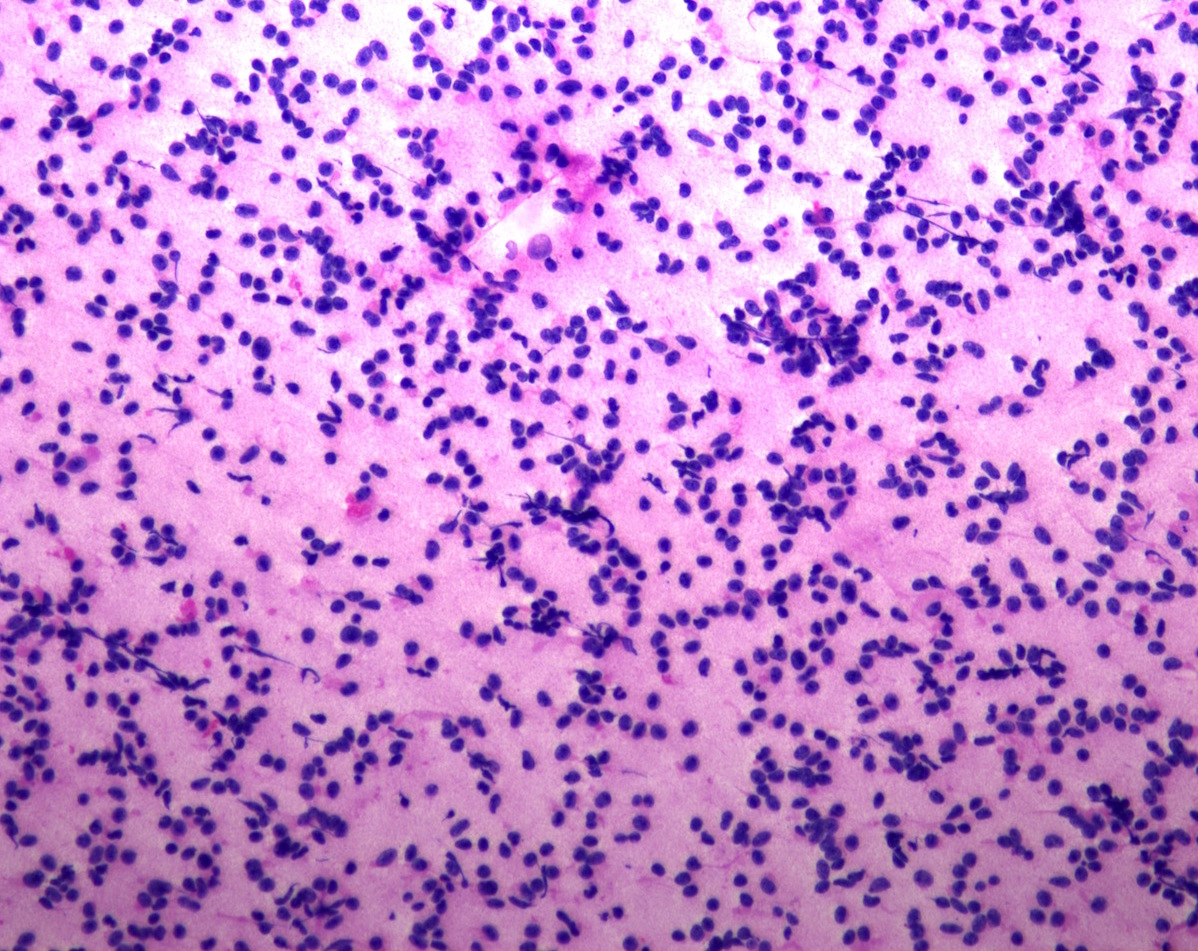

Cytology description

- Normal pituitary has mixed cell types on smear preparation whereas tumors show uniform morphology and cell type

- Tumors produce cellular smear with discohesive small round blue cells

- Some tumors have specific cytologic atypia (e.g., fibrous bodies of sparsely granulated somatotroph tumors, Crooke hyaline of Crooke cell tumors)

Cytology images